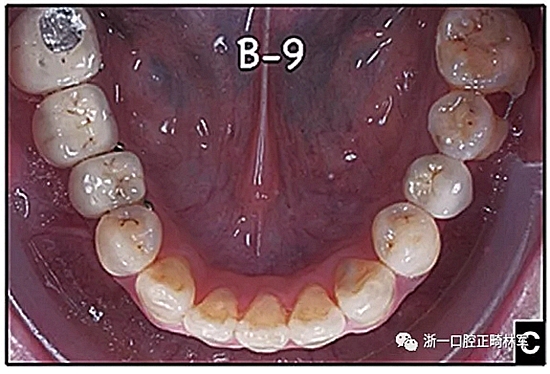

圖15.A,去除固定裝置一個(gè)月后,下頜左側(cè)第二前磨牙復(fù)發(fā),移動(dòng)到種植體愈合的部位; B,B-0表示開始再治療,通過鏈圈和推簧的矯正復(fù)發(fā); C,B-9是治療結(jié)束后3個(gè)月回訪時(shí)下頜弓的咬合面觀,這是再治療階段的9個(gè)月。下頜左側(cè)第二前磨牙和第三磨牙的頰面粘合一個(gè)固定保持器,以防止復(fù)發(fā)。